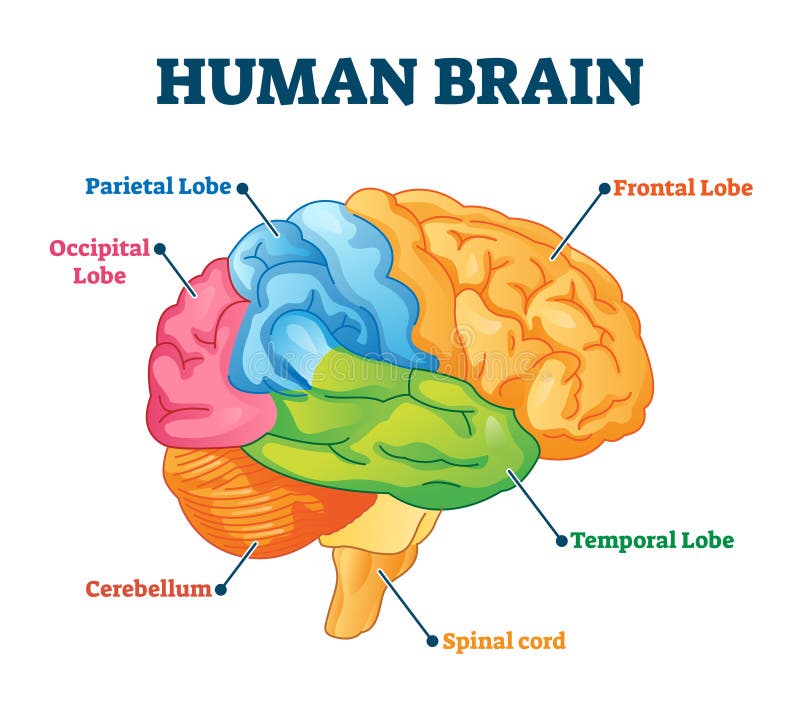

έννοια της τεχνητής νοημοσύνης. άνθρωπος-εγκέφαλος με σύμβολο τεχνητής νοημοσύνης.